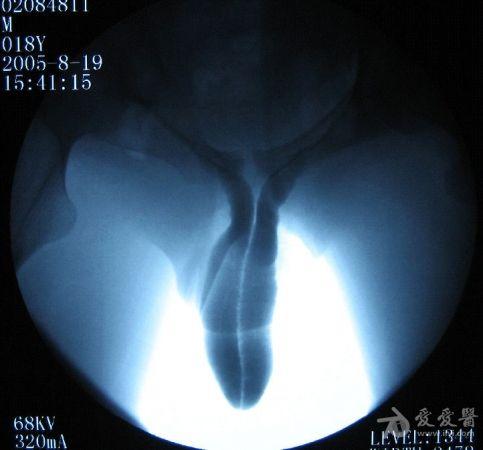

弯曲30度图解男性

弯曲30度图解男性,男人30度向左弯曲图片

生殖整形 正文 在临床医学的诊疗记录中,其实男性朋友阴茎弯曲的

硬核知识:一般来说,弯曲后的阴茎头与阴茎体纵轴夹角小于30度的为